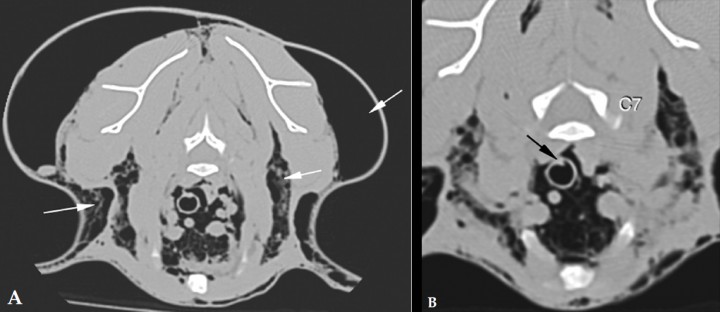

<p>(A) Corte transversal en ventana hueso a nivel de C7. Las fechas blancas señalan enfisema subcutáneo entre fascias. (B) Ampliación de la zona de la traquea. Se observa un defecto a nivel de la pared dorsal de la tráquea (flecha negra).</p>

Figura 6

(A) Corte transversal en ventana hueso a nivel de C7. Las fechas blancas señalan enfisema subcutáneo entre fascias. (B) Ampliación de la zona de la traquea. Se observa un defecto a nivel de la pared dorsal de la tráquea (flecha negra).

Para llegar a un diagnóstico definitivo podrían ser útiles una tomografía computarizada (TC) o una traqueobroncoscopia. En este caso debido a la historia clínica del paciente se decide hacer una TC. El estudio incluye dos series precontraste procesadas con algoritmos de tejido blando y pulmón, con cortes contiguos de 1 mm de grosor. Se observa dilatación marcada del mediastino con gas, o neumomediastino (Fig. 3), así como neumotórax y compresión de lóbulos pulmonares con atelectasia secundaria. El gas del mediastino se extiende a lo largo de los planos fasciales de los tejidos subcutáneos, causando enfisema muy marcado en cabeza, cuello, pared torácica y pared abdominal. El aire también se extiende caudalmente al espacio retroperitoneal (Fig. 4), cabeza (Fig. 5) y cuello (Fig. 6). Se detecta un pequeño defecto en la pared dorsal de la tráquea, aproximadamente a nivel de C7-T1 (Fig. 6B). Se observa mineralización a nivel del riñón derecho.